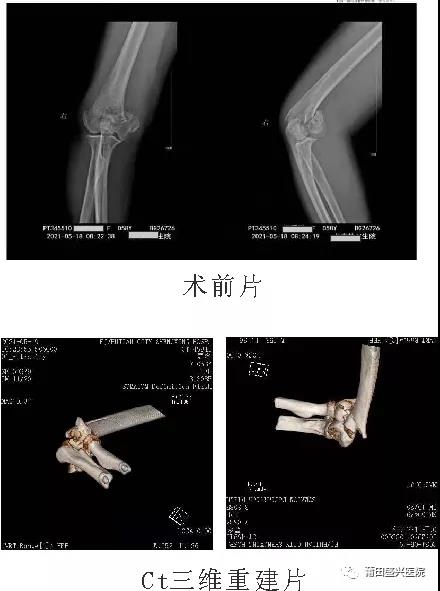

日前,有一女性患者王xx,右肱骨髁間粉碎性骨折,經(jīng)過(guò)與家屬及本人溝通后,我院業(yè)務(wù)副院長(zhǎng)……